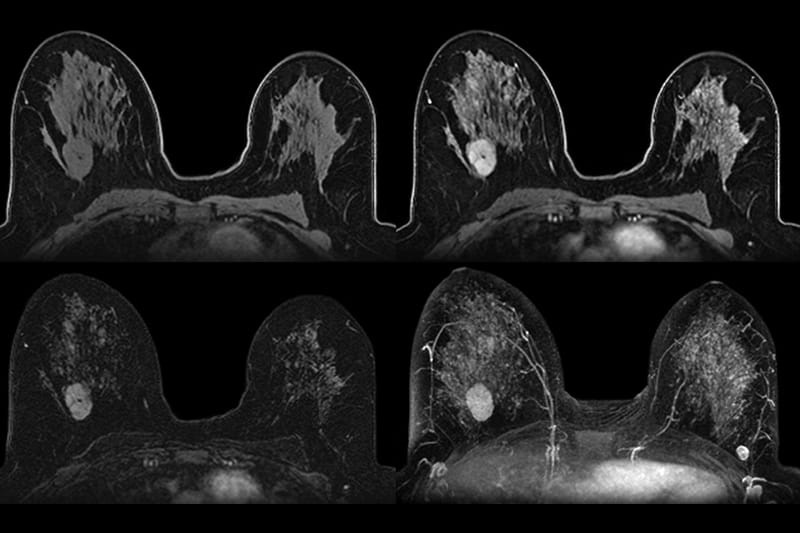

Radiômica e segmentação

Extração automática de centenas de features quantitativas de imagens (TC, PET, RM) para estadiamento preciso, delimitação de tumores e suporte ao planejamento cirúrgico.